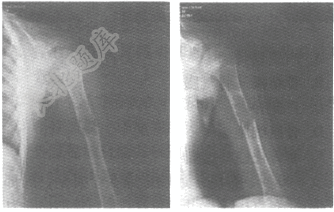

- 单项选择题男,8岁,左上臂外伤后疼痛2小时,结合左肱骨正、斜位片,最可能的诊断是

A、骨嗜酸性肉芽肿

B、非骨化性纤维瘤

C、尤因肉瘤

D、骨囊肿

E、骨肉瘤